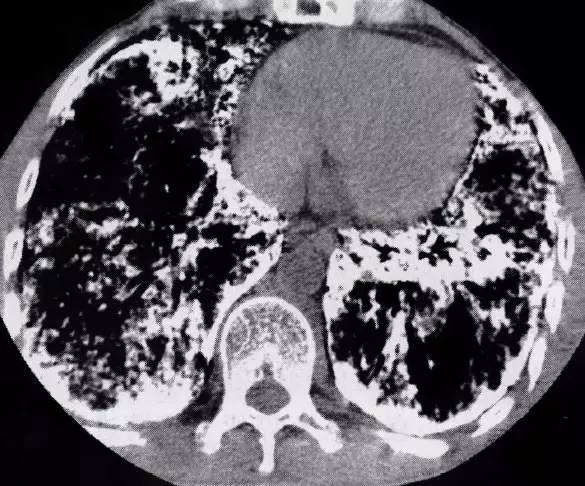

图1肺泡微石症

双肺实质满布弥漫性砂粒状高密度影,双肺后部融合呈高密度片

CT平扫肺窗均显示两肺实质内满布似沙粒状的高密度阴影,其中可见短条状高密度阴影呈放射状分布。肺内有微小结节并融化成大结节状,主要分布于中下肺野的外围。直径多在1mm左右。在紧邻纵隔或背侧的胸膜下区,粟粒结节甚至密集融合,形成大小不一的薄层致密带,融合微石的CT值200~400HU。出现不同程度肺气肿或肺大泡改变,呈广泛的胸膜下多发性微小囊泡,即肺边缘与胸壁之间有薄层气泡样透亮带,内见多个细条状间隔,从肺尖延续到肺底。有散在的间质纤维化,表现为不规则的细索条或网纹状影。因肺野密度普遍增高、衬托对比而形成支气管充气像,部分叶完全楔形实变(图1)。